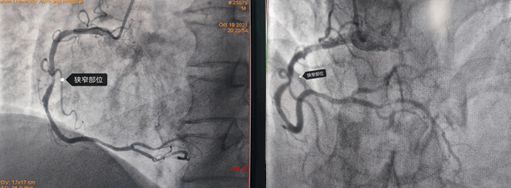

2021年10月19日,64岁的马先生因胸闷、心悸等症状入住心血管九病区,马先生有高血压、吸烟等冠心病危险因素,心电图有心肌缺血表现,为明确马先生是否为冠心病所致上述症状以及决定下一步诊治方案,给他进行了冠脉造影检查,结果如下图:

造影结果右冠多处狭窄约70-90%,左冠也是多处70-80%狭窄;对于这样一个结果,是这些狭窄造成的胸闷、心悸吗?这些病变需不需要都给予介入处理呢?一根血管植入支架还是三根血管都需要植入支架?心内九科崔旭辉主任带领介入医生团队讨论后,决定进行RFR检查给出一个明确的答案。所以经过与患者及其家属沟通后选择进行RFR检测,结果如下图: